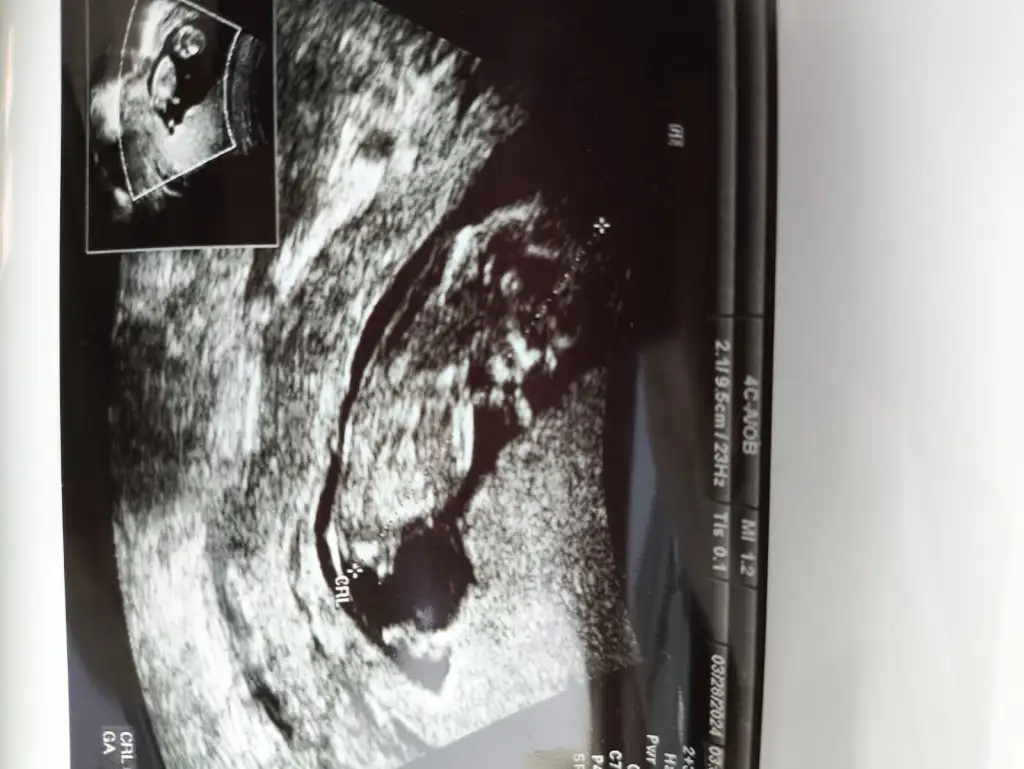

10+2 günlük 3. Aşkım bebekimmm

Kızzzz bunun tipi o poposu nedir Allahım misket limonu kadar ama heryeri var maşallah sübhanallah sağsalim gelsin inşallah annesiBenim tospiğime bi bakar mısınız kordonu bileğine mi dolamış o neCuma günüydü randevum yine cinsiyet tahmini alabilirim sizlerden Totosu çok tatlı değil mi ayy ısırıcam nazar değmesin Sizlerden de fotolar bekliyorum güzel anneler. Birbirimize nazarımız olmaz bence